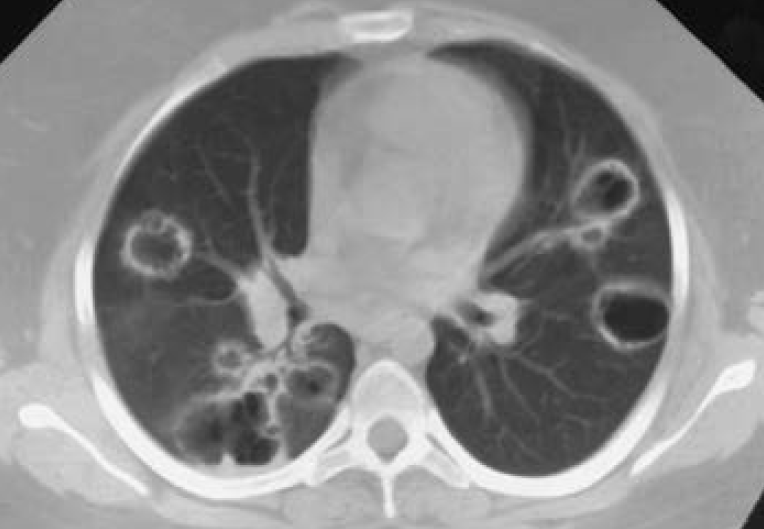

② 영상검사: 흉부 CT - nodular cavitary infiltrates

(4) 진단: 조직검사(주로 폐생검, 신생검) → 육아종을 동반한 necrotizing vasculitis